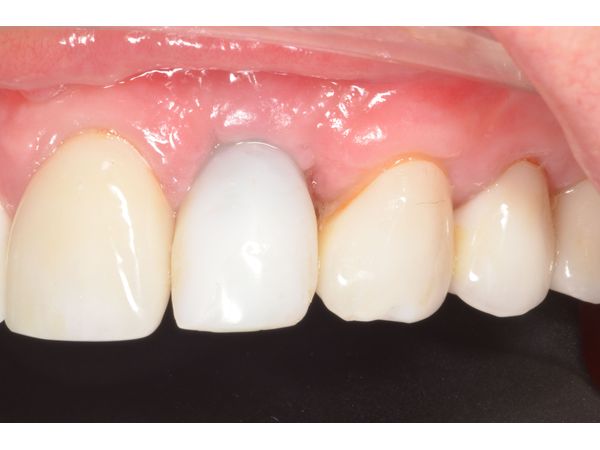

Одновременно с этим изготовили временную коронку из пластмассы на титановом основании.

Через 3 месяца после интеграции импланта временную коронку заменили на постоянную циркониевую коронку.